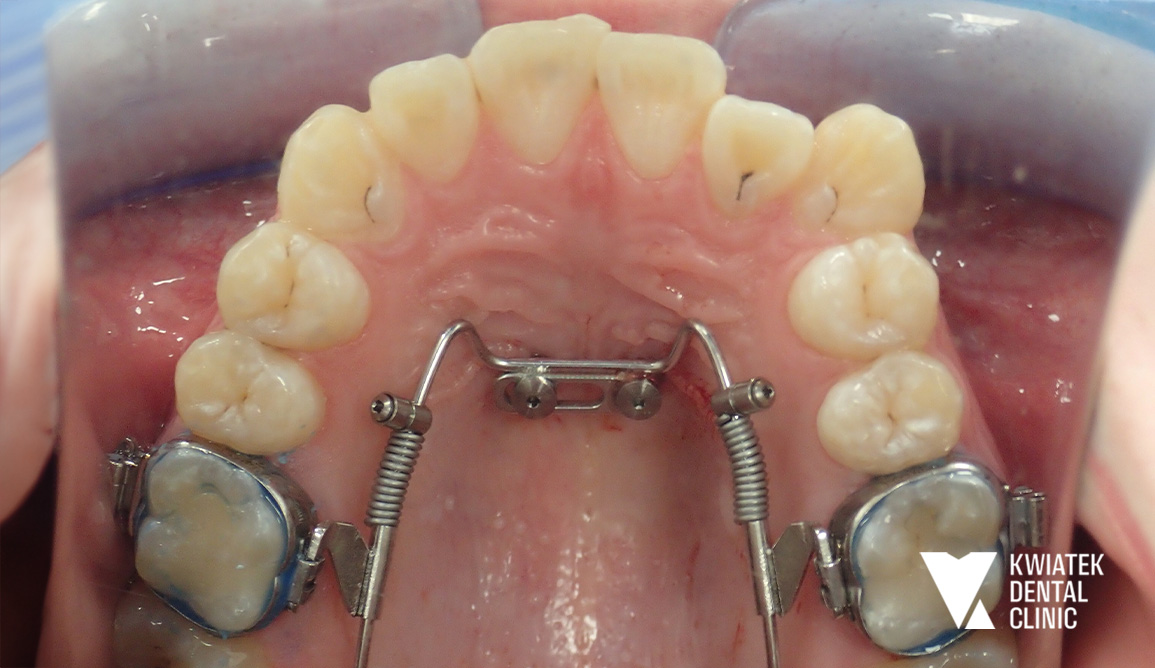

PRZED

3. zastosowanie systemu ortodontycznego Beneslider opartego na miniimplantach podniebiennych

Leczenie rozpoczęto od profesjonalnej higienizacji jamy ustnej. Podczas wizyty stwierdzono znaczne nagromadzenie płytki bakteryjnej oraz kamienia nazębnego w przestrzeniach międzyzębowych, dlatego przeprowadzono dokładny instruktaż higieny oraz zalecono odpowiednie preparaty remineralizujące. Następnie wykonano chirurgiczne usunięcie zębów mądrości. Kluczowym etapem terapii było zastosowanie systemu Beneslider. Na podniebieniu wprowadzono dwa miniimplanty ortodontyczne o wymiarach 2.0/11 mm w znieczuleniu nasiękowym. Na zębach 16 i 26 osadzono pierścienie, a następnie zamontowano aparat dystalizujący umożliwiający przesunięcie zębów trzonowych do tyłu i uzyskanie przestrzeni w łuku. Po uzyskaniu odpowiednich warunków przestrzennych rozpoczęto leczenie aparatem stałym cienkołukowym zamkami samoligaturującymi. Aparat założono w obu łukach zębowych, a Pacjent otrzymał szczegółowy instruktaż higieny oraz zestaw ortodontyczny do codziennej pielęgnacji. W kolejnych miesiącach regularnie wykonywano wizyty kontrolne, podczas których aktywowano aparat, stosowano łuki ortodontyczne o różnej sztywności oraz elementy dodatkowe. W trakcie leczenia przeprowadzono także leczenie zachowawcze z użyciem materiałów kompozytowych w koferdamie i pod kontrolą mikroskopu. Równolegle wykonywano okresowe higienizacje oraz kontrolowano stan jamy ustnej, aby utrzymać zdrowe środowisko podczas terapii ortodontycznej.